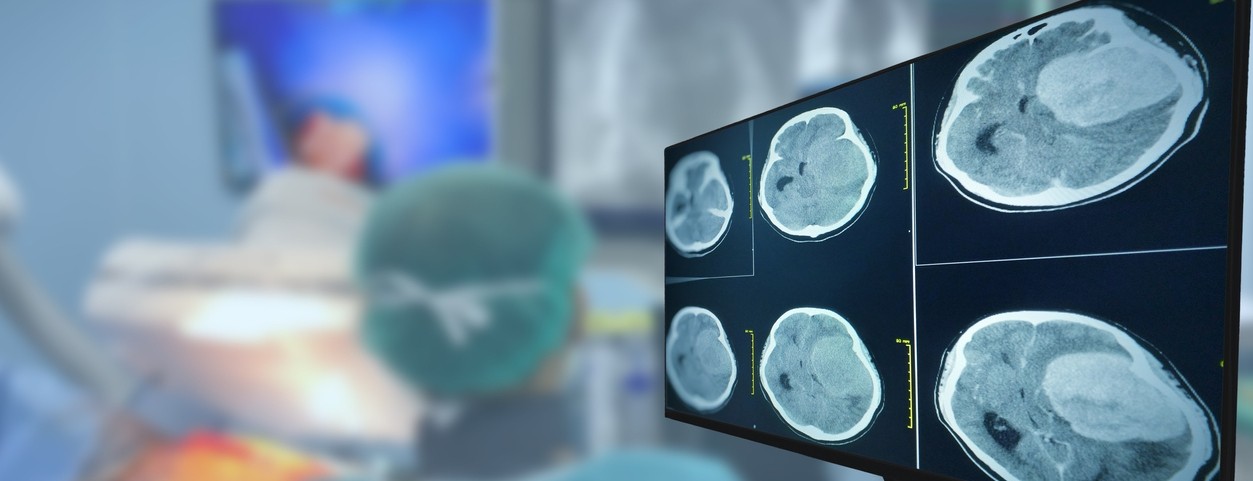

New research out of the University of Cincinnati shows a targeted drug therapy had positive results in delaying the progression of a specific form of glioma, which is a slow-growing brain tumor.

Researchers studied 331 people with this disease and compared the study drug to a placebo. Those given the targeted therapy did not have disease progression for more than 27.7 months. For those in the placebo group, it was only 11.1 months.